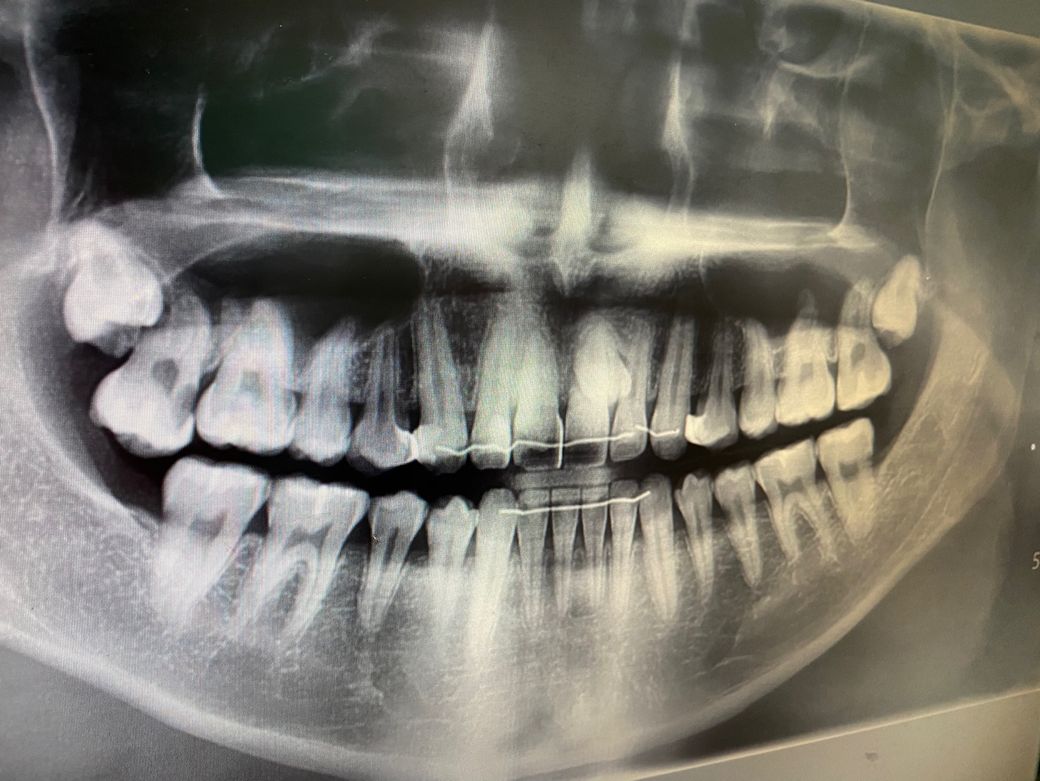

아니면 엑스레이를 찍어봐야 알 수 있을까요?

이틀 전까지 신경치료를 받느라 치과에 다니고 있었는데 갑자기 저런 것이 보이니 당황스럽네요.

우선 현재로써는 분명하지는 않으나 충치나 착색의 가능성이 높아보이며 보다 정확한상태한 파악을위해 빠른 시일내에 치과를 방문하여 진료를 받으시길 권장드립니다.

직접 검사를 해봐야 알 수 있으며 충치보다는 단순변색으로 보이기는 하며 두 경우모두 간단하게 치료할 수 있는 범위같습니다

예전에 치료 받은부위에 틈이 생겨서 착색 및 2차 충치가 생기신거 같습니다. 치과에 가시면 다시 치료를 받으셔야될수도 잇을것같습니다.